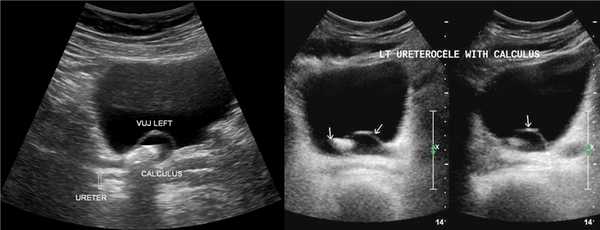

На УЗИ в мочевом пузыре или в уретре определяется анэхогенное образование, округлой формы, с четким и ровным контуром; соответствующий мочеточник обычно заметно расширен; может присутствовать гидронефроз верхней части удвоенной почки. Уретероцеле определяют как внутрипузырные (полностью внутри мочевого пузыря) или внепузырные (некоторая часть постоянно расположена в шейке мочевого пузыря или в уретре).

Уретероцеле может варьировать в размерах от крошечной кистозной полости до большого баллона, который заполняет мочевой пузырь. Прогноз связан со степенью обструкции и рефлюкса. Важно измерить толщину и эхогенность почечной паренхимы, чтобы оценить степень повреждения почек.

Рисунок. На УЗИ в уретероцеле определяется гиперэхогенная структура с акустической тенью — камень. Уретероцеле может являться одним из факторов, способствующих камнеообразованию.